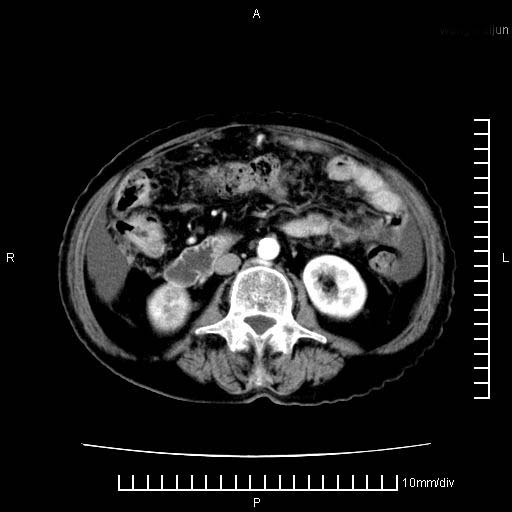

上腹疼痛月余,外院核磁诊断胰腺癌。现临床示右下腹可明显触及包块,可片子上怎么没有看到?

1.胰腺颈体部癌。

2。腹腔积液。

3。右胸腔积液,伴右肺下叶部分萎陷。

4。右肾盂囊肿。

胰腺体部癌累及周围器官,腹膜、粘连

1。胰腺ca伴腹膜腔转移

2。肝左叶低密度灶,考虑转移可能

胰腺体部癌累及周围器官,腹膜、粘连,临床摸到的可能是粘的组织

胰腺结构模糊,胰尾部见囊性包块,周围脂肪密度增高,左肾前筋膜增厚,胸水、腹水。不符合胰腺ca伴腹膜腔转移。考虑胰腺炎伴假性囊肿形成、胸腹腔积液。

右肾盂囊肿。

1)考虑胰腺癌并胰腺假性囊肿形成。2)肝内低密度灶,不排除转移。3)右肾盂积水。4)腹水。5)右侧胸腔积液并右肺下叶部分膨胀不全。